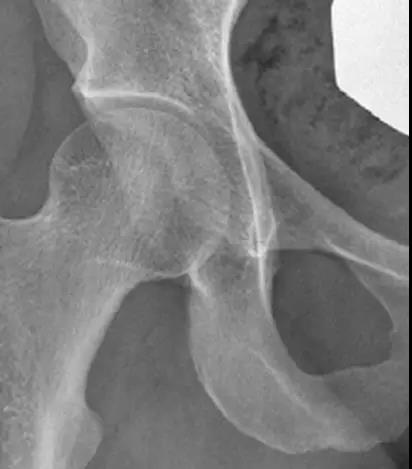

凸轮撞击型FAI▼

- 股骨头颈间的凹陷不足,伴局部的骨质增生。

- 股骨头颈的“ 枪柄样” 畸形。

- 偏心距是水平位投照平片上平行的股骨颈切线与股骨头前缘之间的距离。

- 正常值为11.6mm。

- FAI偏心距缩短<7.2mm。